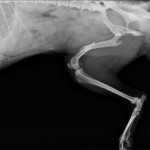

Снимок кошки страдающей от сердечных заболеваний.

Симптоматика перечисленных патологий весьма схожая, так имеет общий корень развития. У питомцев наблюдается одышка, приступы удушья, обмороки, сильный кашлевой синдром. Характерным признаком также бывает асцит – наполнение жидкости в брюшной полости. Снижение температуры, быстрая утомляемость, слабость.

Диагностика сердечных болезней

Диагностируют болезни сердца путём сбора анамнеза, визуальный осмотр, тактильный. Измеряют давление, проводят электрокардиографию, рентгенографию, эхокардию.